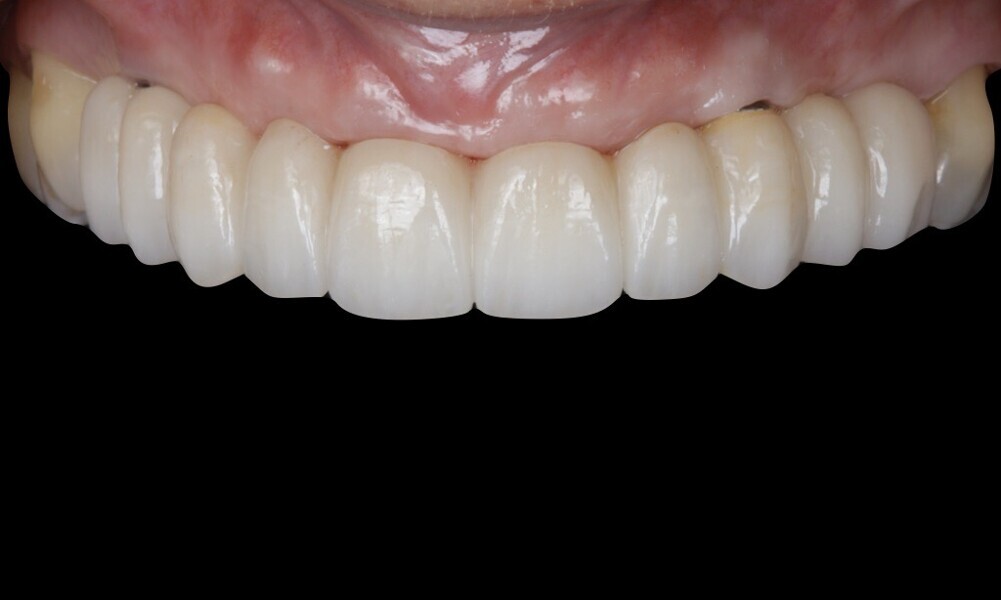

The soft tissue was in good condition, and the definitive restorations were placed (Figs. 76 & 77). After placing the definitive restorations, oral hygiene instructions were given to ensure proper care and prevent complications. Additionally, the occlusion was carefully checked and adjusted as needed (Figs. 78–83).

Figs. 78–82: The definitive restorations were placed, and occlusal adjustments were performed.

Treatment outcomes

Good results were achieved regarding both hard and soft tissue, as well as aesthetics. The patient shared the following testimonial: “I couldn’t be happier with my new smile! The process was so precise and seamless, and I felt involved every step of the way. The digital planning made it clear what to expect, and the results are beyond what I imagined—natural, beautiful and perfectly suited to me. Eating and smiling feel effortless again. It’s truly life-changing!”